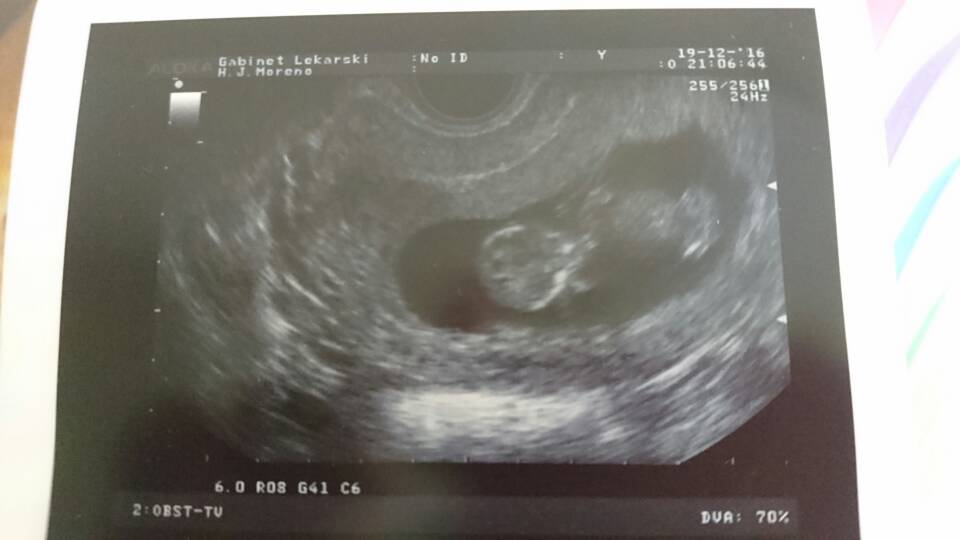

Pochwalę się moimi zdjęciami z usg - nie są tak wyraźne jak u Was, ale i tak wczorajsza wizyta wzruszyła mnie na maxa [emoji4]. Wg usg wychodzi nam 12 tc. Wzrost - 4,8 cm.

Zobacz załącznik 788313Zobacz załącznik 788314